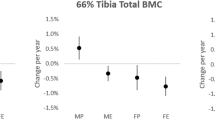

At baseline, no differences were found in bone traits between EX and CTRL, except in vBMDTOT and vBMDCO of the tibial midshaft, which were 2–3% higher in EX (p = 0.002 and 0.001, respectively). The intervention had no effect on distal tibia bone traits (Supplementary Table 1). The effect of the training on the tibial midshaft is shown in Table 2, Supplementary Table 2 and in Fig. 2. The average difference in change in ThCO in EX compared to CTRL was 2.0% (p = 0.007) across the whole EX group and 2.8% (p = 0.008) in the group aged 65–85 (EX, n = 17; CTRL, n = 16). The corresponding differences in I minA were 1.9% (p = 0.034) across the whole EX group and 2.8% (p = 0.031) in the group aged 40–64 (n = 21 and 14, respectively).

Per protocol analysis

As in intention-to-treat analysis, no changes were detected in the distal tibia bone traits. The effect of the training on the tibial midshaft bone traits is shown in Tables 3 and 4 and in Fig. 2. In the EX compared to CTRL group, CSATOT increased by 1.6% (p = 0.013), CSACO by 1.8% (p = 0.007), and ThCO by 2.6% (p = 0.012). In the area and density-weighted moments of inertia, the increase in favor of EX was 3.2% for I minA (p = 0.006), 1.8% for I minD (p = 0.023), and 2.0% for I polarA (p = 0.035). In the EX compared to CTRL group, BMCTOT increased by 0.7% (p = 0.017), whereas the changes in density favored CTRL (vBMDTOT 0.9%, p = 0.035 and vBMDCO 0.8%, p = 0.043). The polar mass distribution analysis revealed a significant group × time interaction at the A-M site. In EX compared to CTRL, BMCA-M increased by 2.2% (p = 0.051).